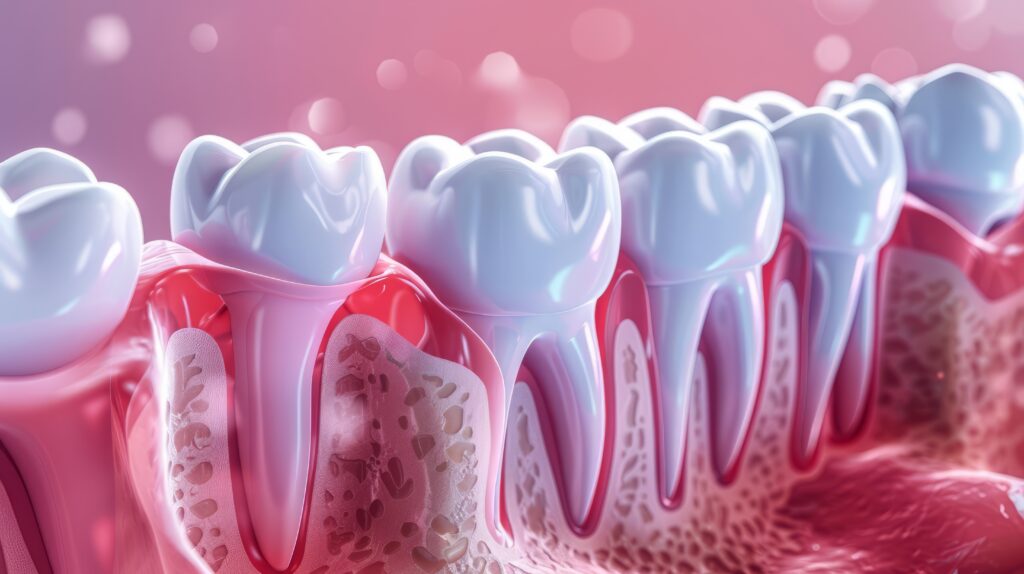

歯肉が腫れている、歯磨きで出血するという状態は、歯周病が進行している可能性があります。歯周病は、歯を支えている骨が少しずつ溶けていく病気で、進行すると最終的に歯が抜けてしまうこともある状態です。

詰め物や被せ物は、歯の形を正確に再現することでぴったりと適合します。しかし、歯肉に腫れや出血があると、型取りの際に正確な形が取れず、適合が悪くなる可能性があります。

歯肉の状態が不安定なまま治療を行うと、被せ物との間に微細な隙間ができることがあります。この隙間から細菌が入り込むことで、二次むし歯のリスクが高くなります。

歯周病治療の基本となるのが、歯石の除去や歯の根の清掃です。これにより、歯肉の炎症を抑え、健康な状態へと導きます。

歯肉の腫れや出血が改善されることで、正確な型取りが可能になります。歯肉が健康で引き締まっている状態では、歯と歯肉の境目が明瞭に把握できるため、細部まで精密に再現することができます。

歯肉と歯の状態が安定していることで、補綴物も長持ちしやすくなります。炎症がある状態では、歯肉の位置が変化しやすく、後から段差や隙間が生じる原因になりますが、健康な歯肉ではそのリスクが低くなります。